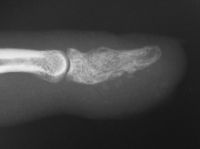

| Because the palmar cortex appeared to be the strongest remainig area, a midlateral approach was chosen over a midline volar longitudinal incision. |

| A corticocancellous strut bone graft was placed in the defect to stabilize the weakened bone. |

| Late result. |